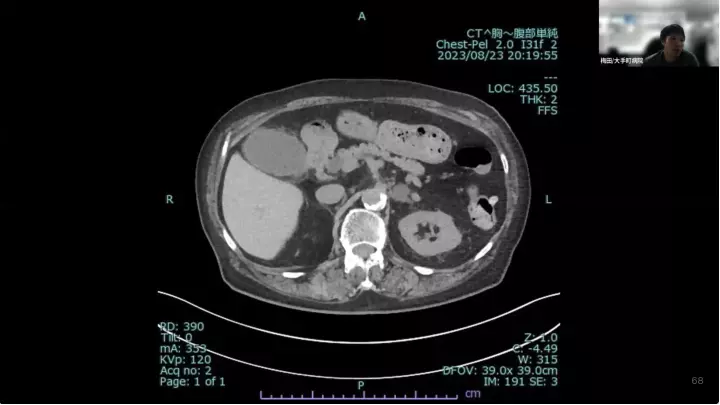

外科医目線の~急性胆嚢炎~治療編